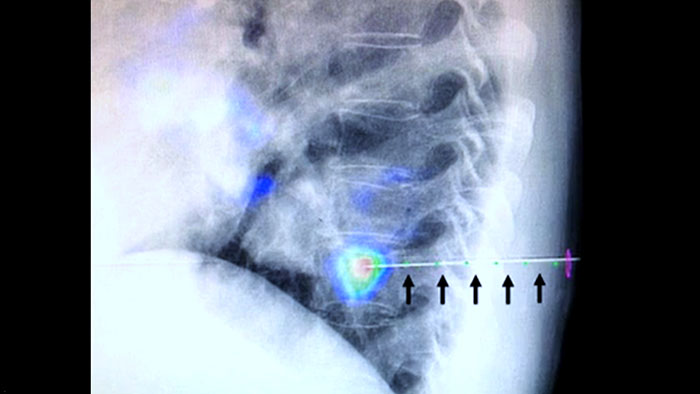

XperGuide provides highly accurate live image guidance of each needle to a targeted position by overlaying pre-planned trajectories with fluoroscopic imaging.3

Lesion heterogeneity and lack of conspicuity limit the quality of specimens as well as the feasibility of biopsies when performed under ultrasound or conventional CT. With the increasing adoption of screening programs in lung, early lung cancers manifesting as small nodules have been detected more frequently than ever before. 14.5% of a screened population was observed to have nodules ≤10 mm.1-2 Our needle navigation technology with CBCT increases precision, and enables the targeting of smaller (<=1 cm) or heterogeneous lesions more accurately with less needle repositioning and at lower dose than conventional CT.1-2